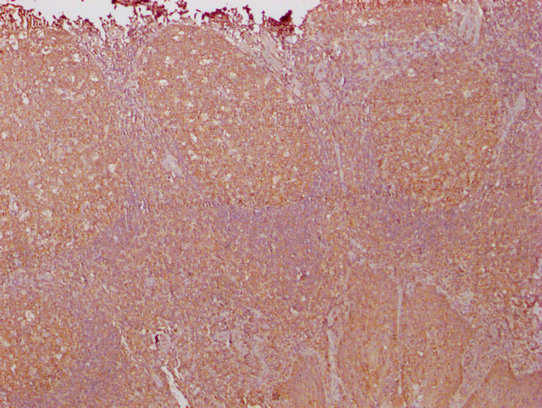

IHC image of CSB-MA018072A1m diluted at 1:1000 and staining in paraffin-embedded human tonsil tissue performed on a Leica BondTM system. After dewaxing and hydration, antigen retrieval was mediated by high pressure in a citrate buffer (pH 6.0). Section was blocked with 10% normal goat serum 30min at RT. Then primary antibody (1% BSA) was incubated at 4°C overnight. The primary is detected by a biotinylated secondary antibody and visualized using an HRP conjugated SP system.